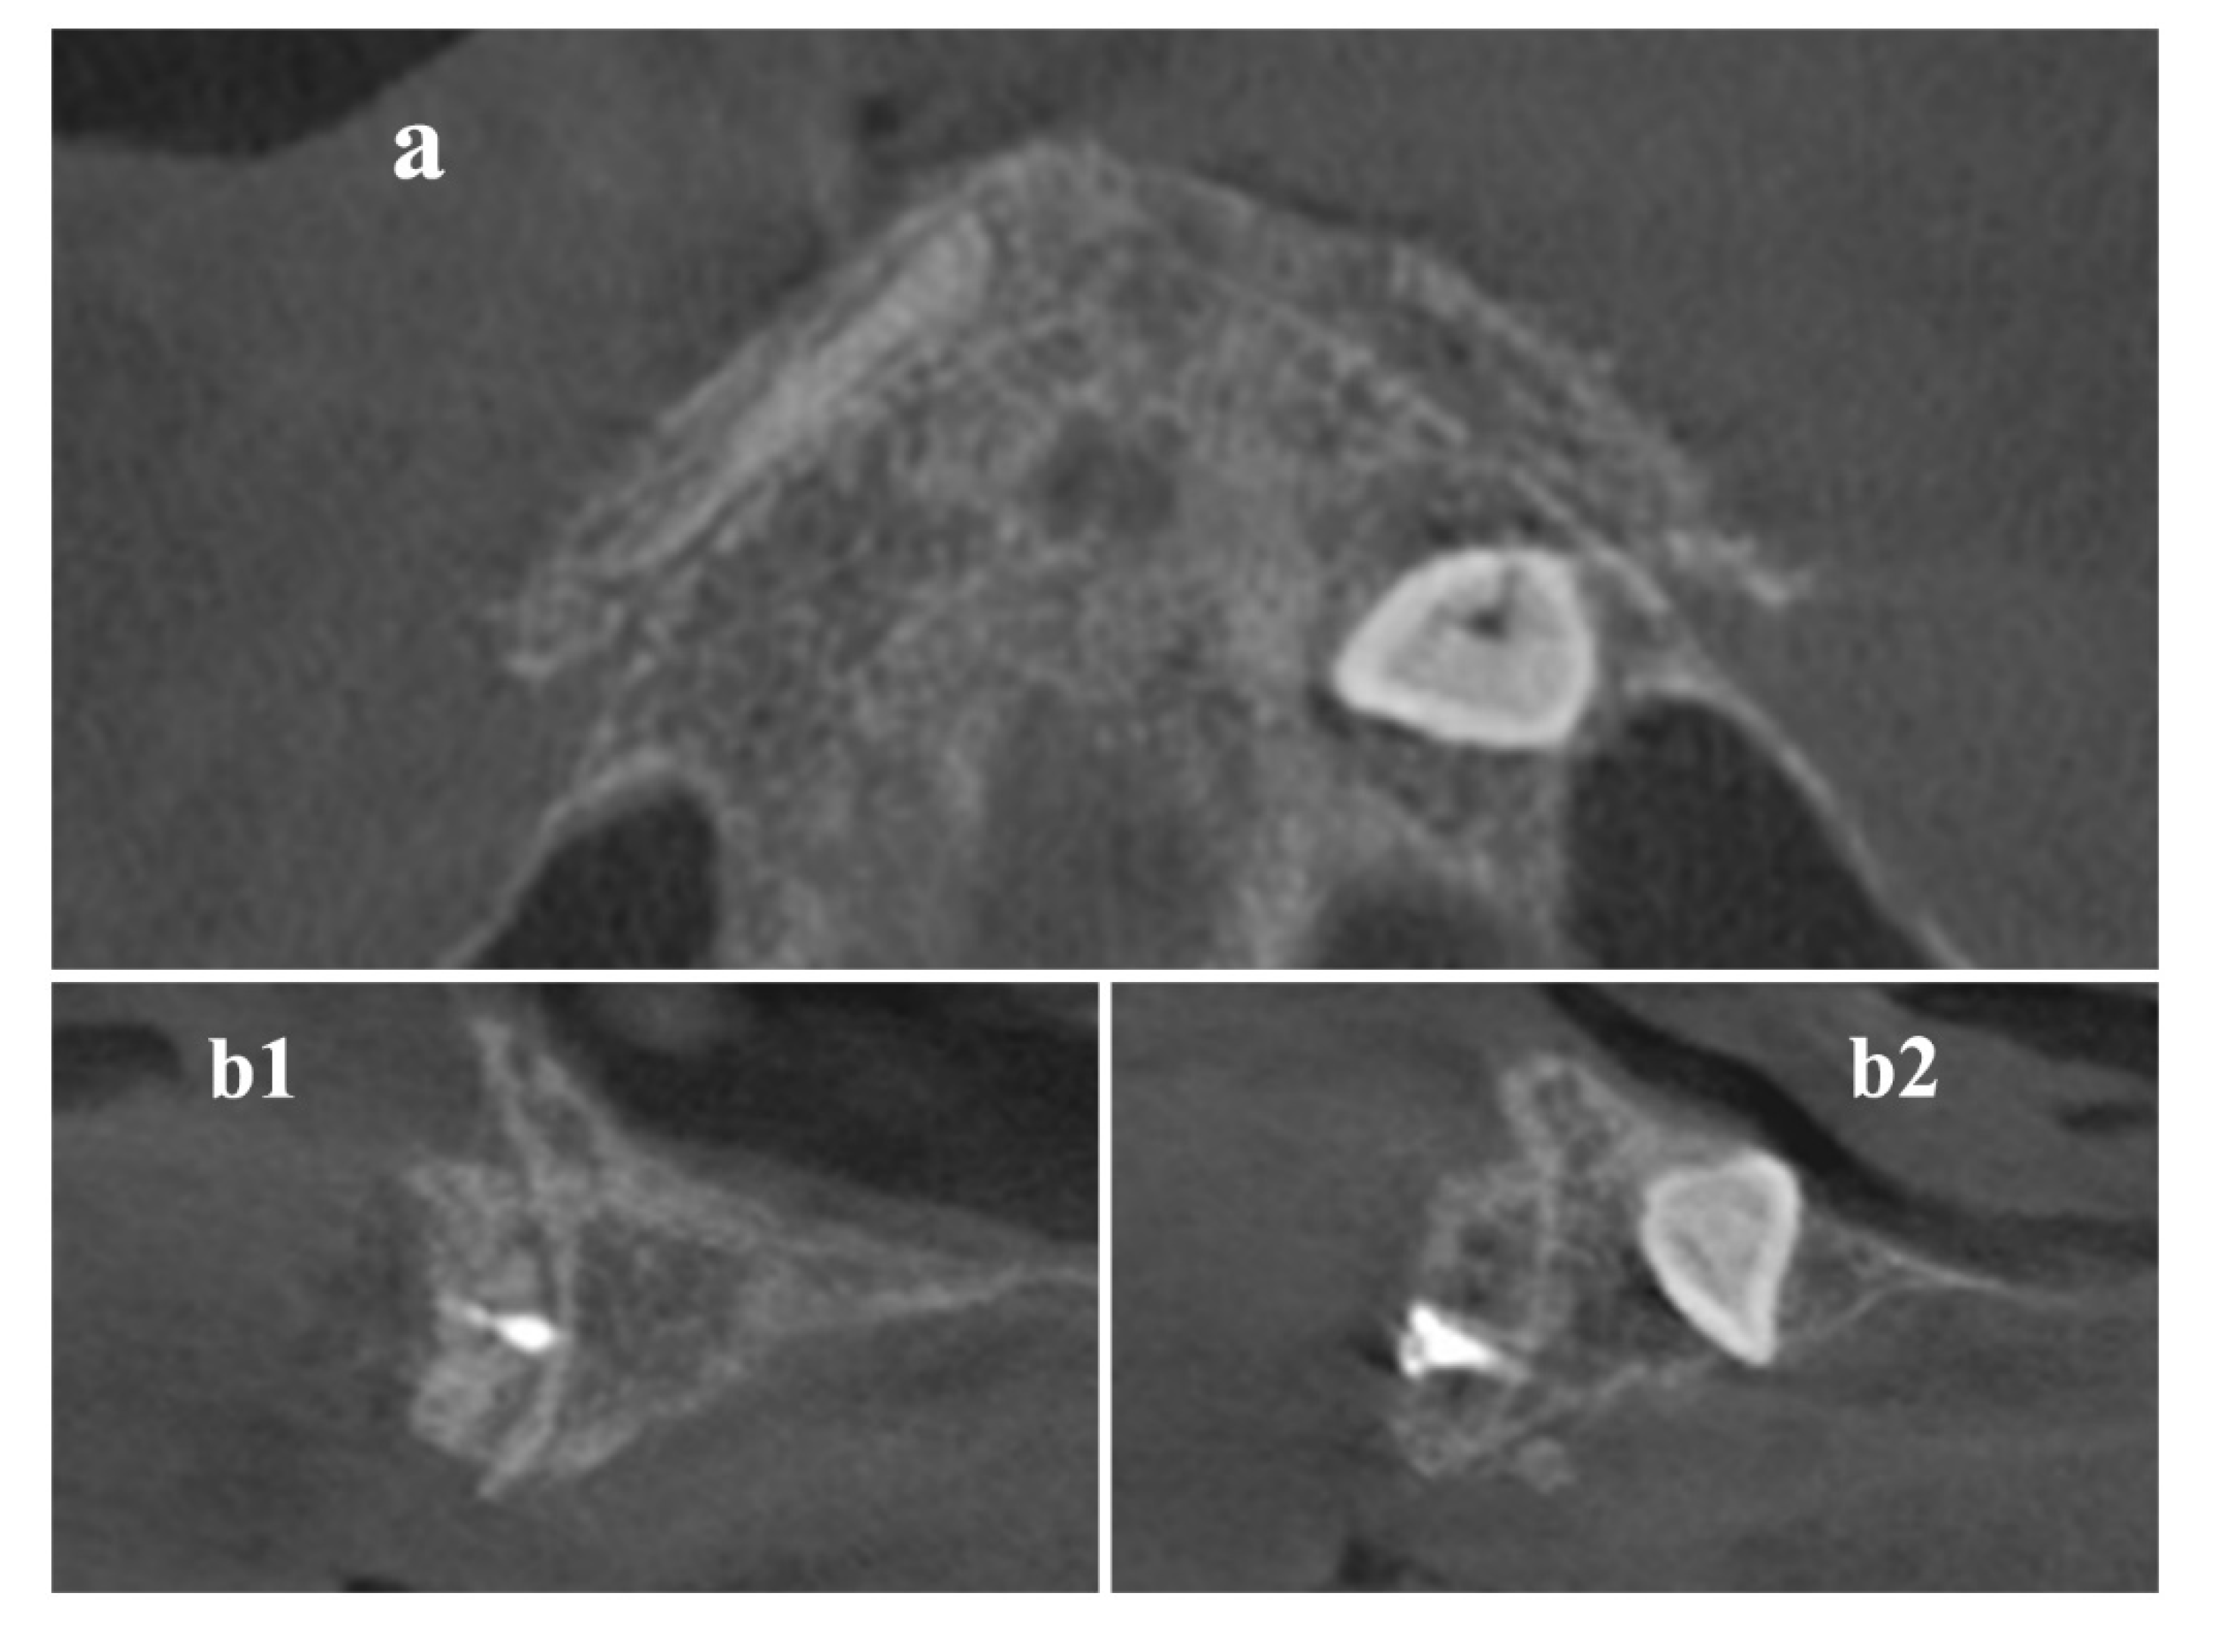

Trajectory Planning and Graft Manufacturing

Surgical Procedure